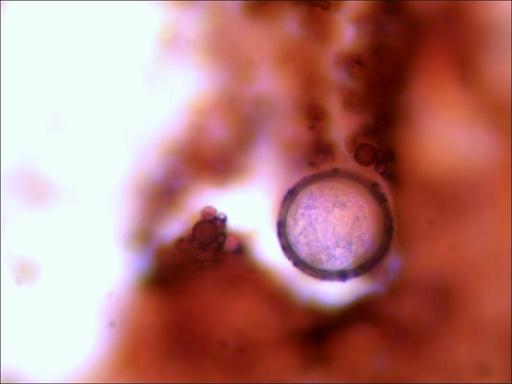

Un par de fotos de unos ooquistes de coccidio en una tincion Gram...... ahi se puede apreciar el grueso de las capas exteriores del huevo, que vistos en fresco no parecen tan gruesas......saludos

- TS_11_27_01_23_42.jpg (14.42 KiB) Visto 2070 veces

- TS_11_27_01_25_21.jpg (14.38 KiB) Visto 2070 veces

Hola a todos ,Manuel esas fotos están muy bien ,el dia que me salga algún pájaro con coccidios lo probare

porque se ven muy bien las diferentes partes del ooquiste, un saludo MANUEL.

Hola compis os pongo unas fotllos como veréis son de un ooquiste de coccidio